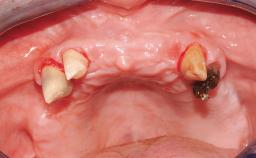

In September of 1995, a 64-year-old female patient presented to our clinic with a distally shortened arch in the left maxilla and the desire for a fixed rehabilitation. The patient’s medical history did not reveal any major issues, and she did not take any significant medication. She was a non-smoker and did not report any allergies.The patient wished to restore her chewing function on the left side, which was severely compromised due to the missing teeth 25, 26, and 27. The antagonistic lower teeth were present and in acceptable condition.

# of Teeth | 2 |

# of Implants | 2 |